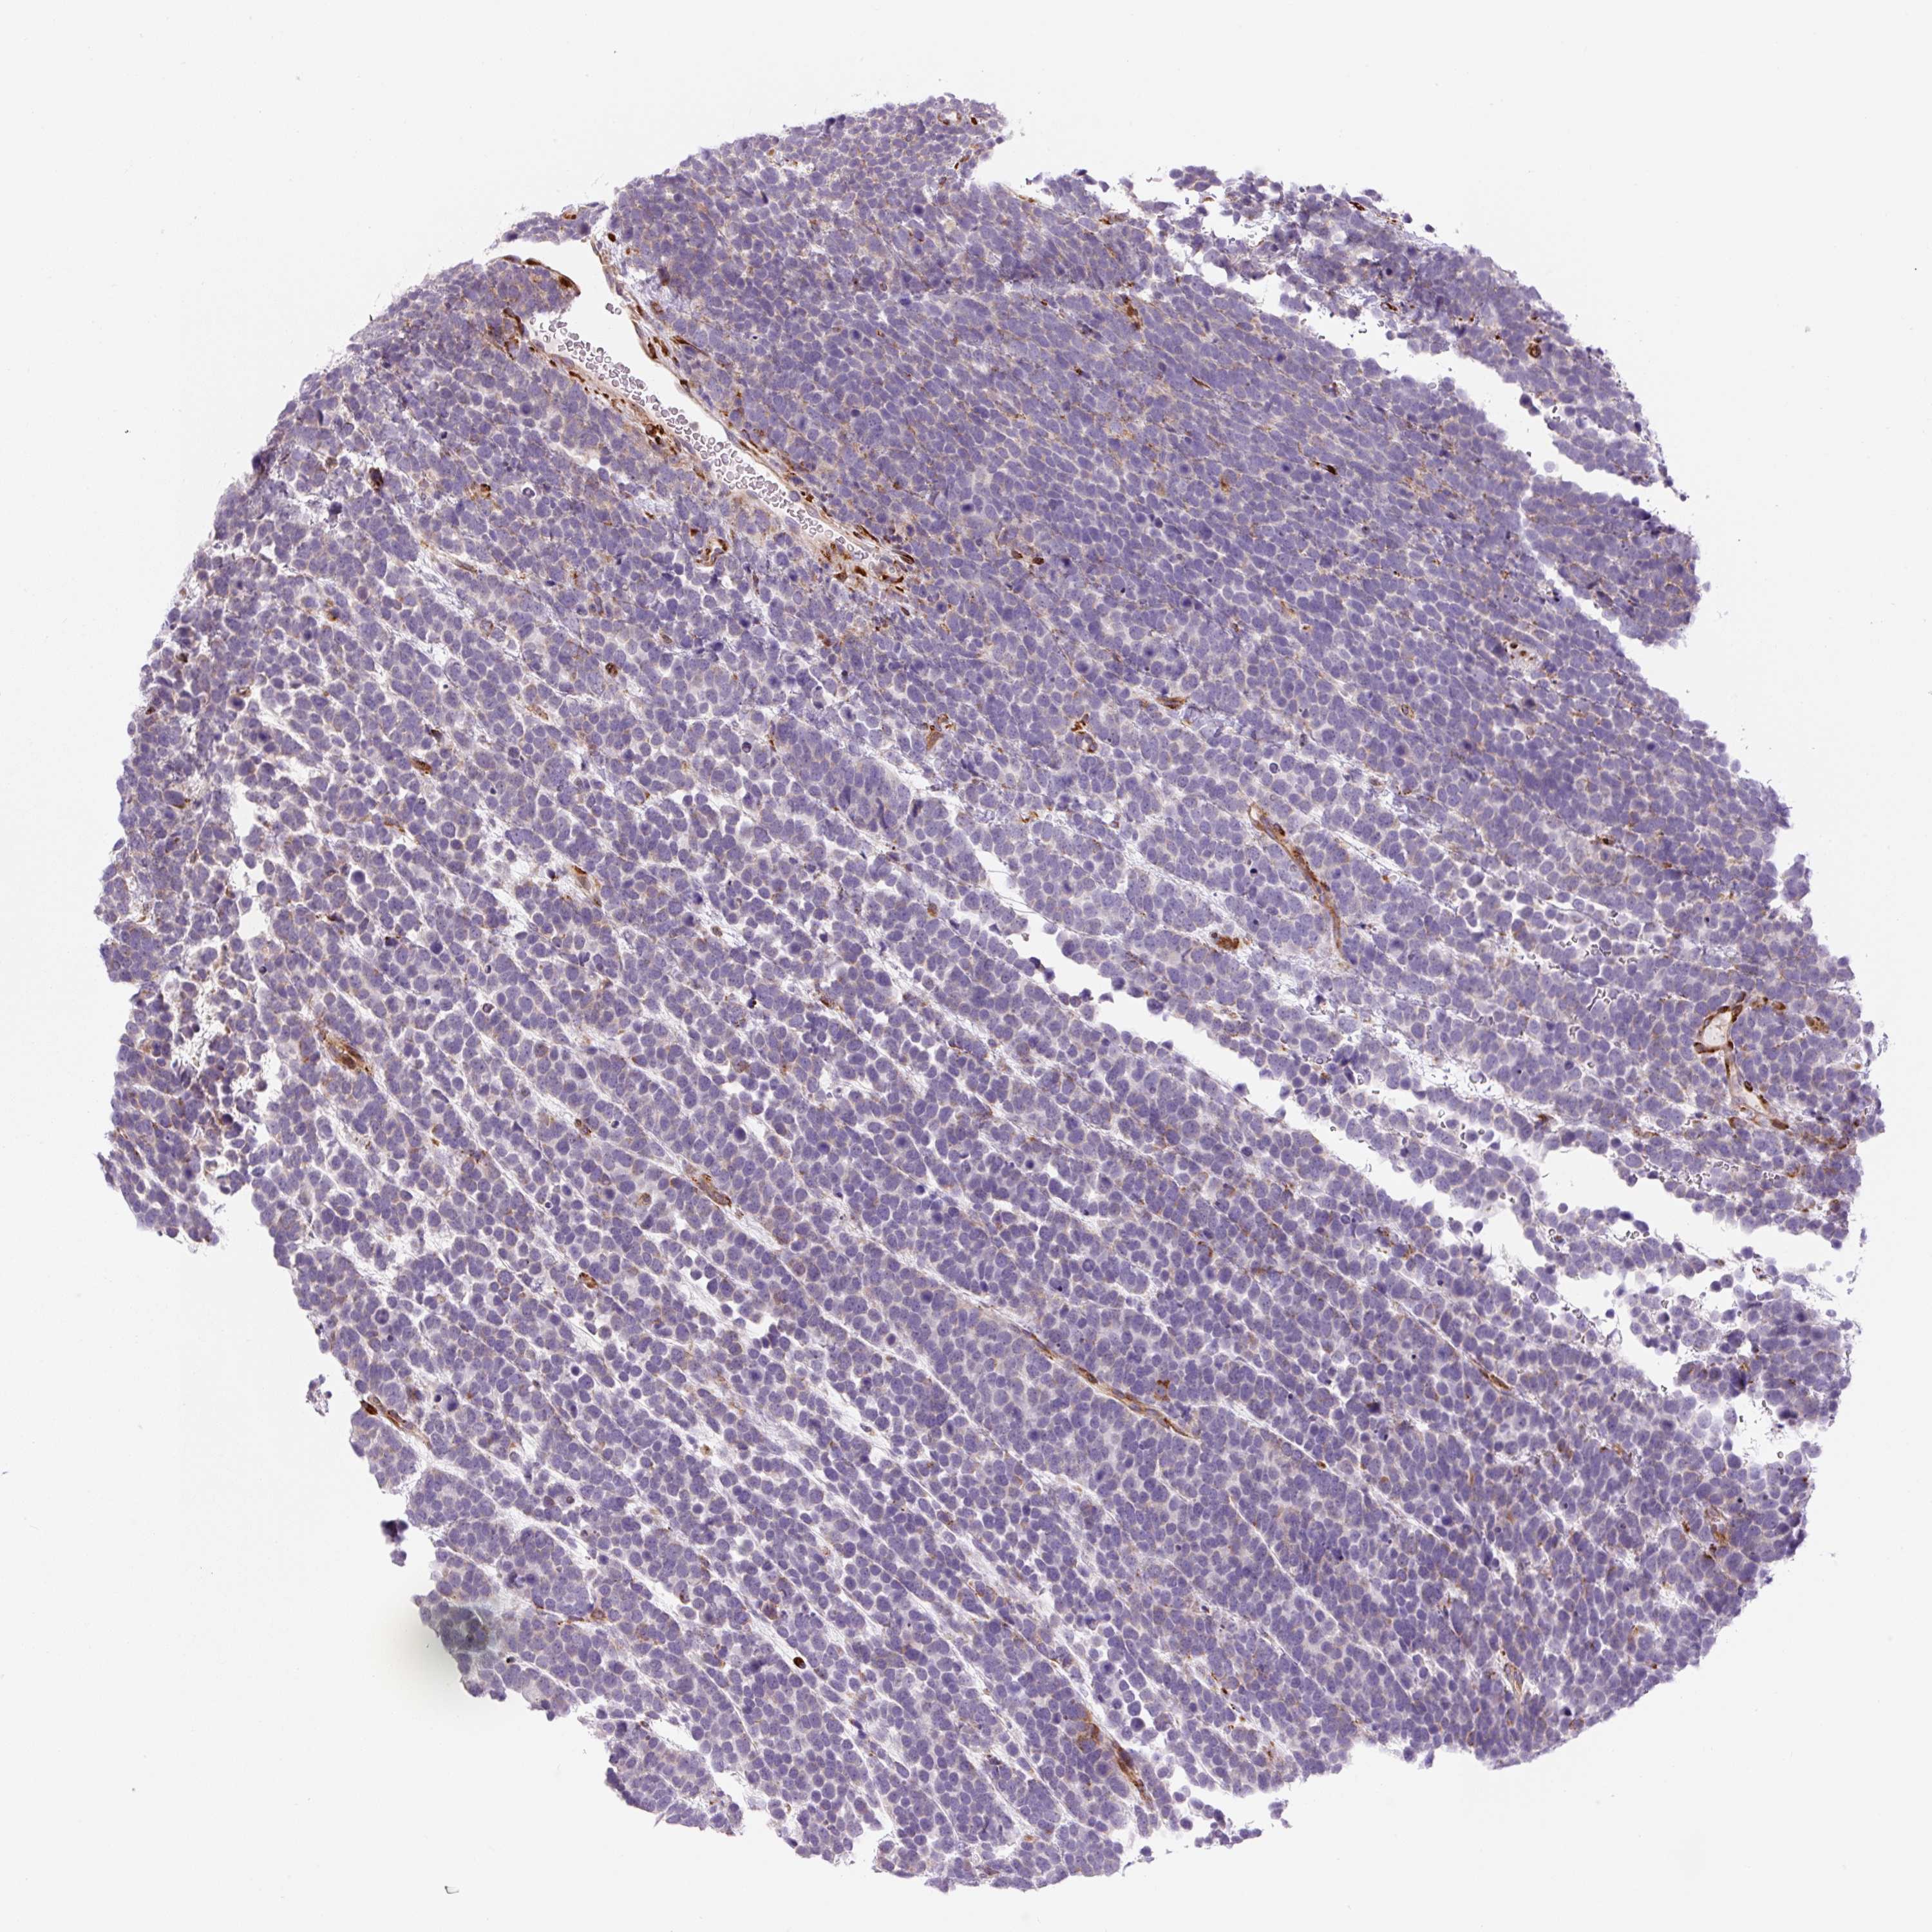

UROTHELIAL CANCER - Protein expressioni

A mouse-over function shows sample information and annotation data. Click on an image to view it in a full screen mode. Samples can be filtered based on level of antibody staining by selecting one or several of the following categories: high, medium, low and not detected. The assay and annotation is described here.

Note that samples used for immunohistochemistry by the Human Protein Atlas do not correspond to samples in the TCGA dataset.

Antibody stainingi

Antibody staining in the annotated cell types in the current human tissue is reported as not detected, low, medium, or high, based on conventional immunohistochemistry profiling in selected tissues. This score is based on the combination of the staining intensity and fraction of stained cells.

Each image is clickable and will lead to virtual microscopy that enables deeper exploration of all samples and also displays staining intensity scores, fraction scores and subcellular localization as well as patient and tissue information for each sample.

Antibody HPA054579

Staining

High

Medium

Low

Not detected

Intensity

Strong

Moderate

Weak

Negative

Quantity

>75%

75%-25%

<25%

None

Location

Urothelial carcinoma, High grade

Urothelial carcinoma, Low grade

Urothelial carcinoma, NOS